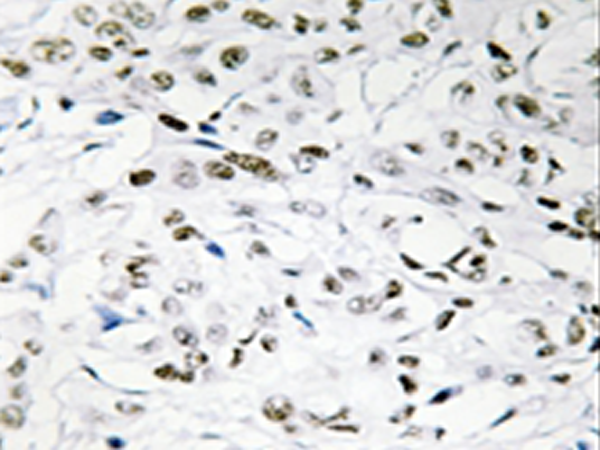

IHC positive control: |

Human breast carcinoma tissue |

IHC Recommend dilution: |

50-100 |